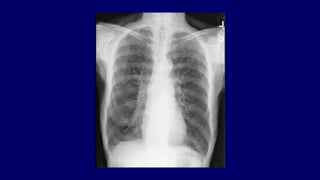

Chest x-ray-Chronic bronchitis

No apparent

abnormality

Or thickened and

increased lung

markings are noted.